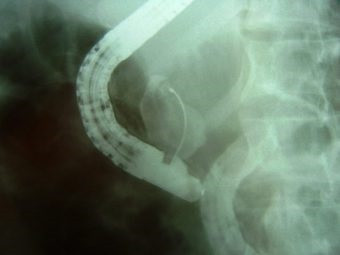

Cálculo gigante y divertículo duodenal ERCP

Envíado por Dr. Carlos Miguel Zavaleta Consuegra